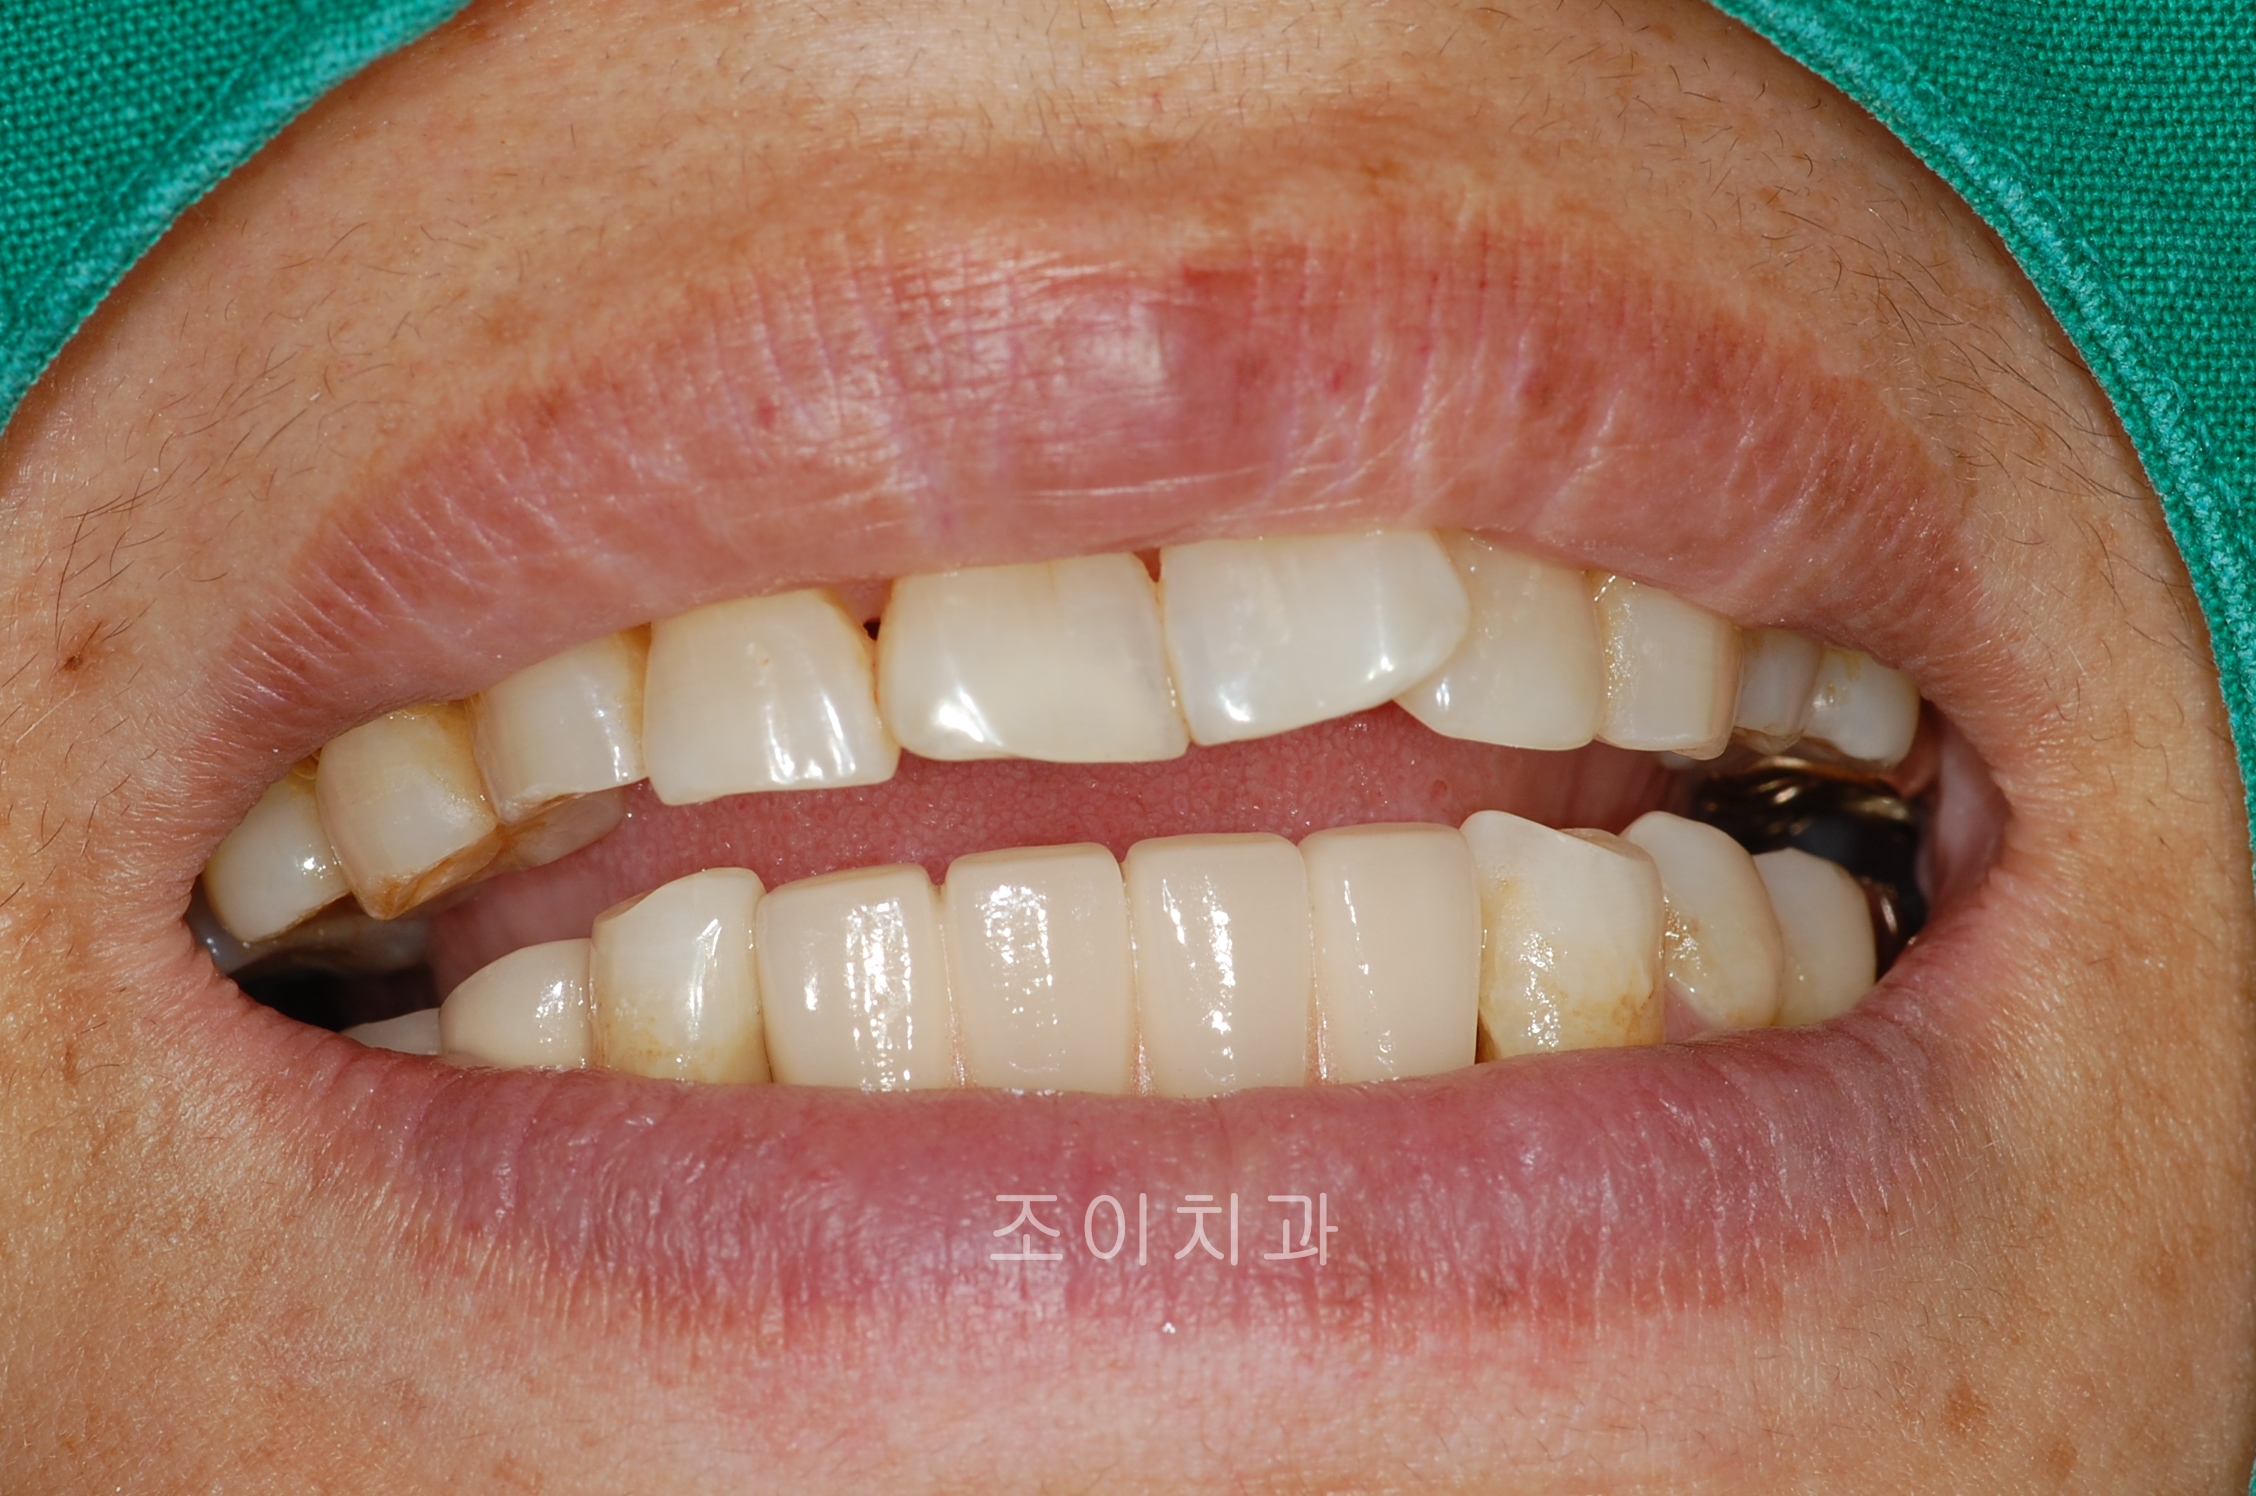

[임플란트] 제목 : 하악전치

임플란트 보철